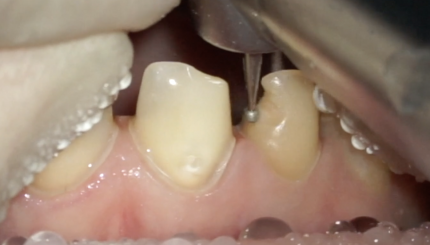

43 42 41 31 32 Финишное препарирование + ретракция

10 августа 2021